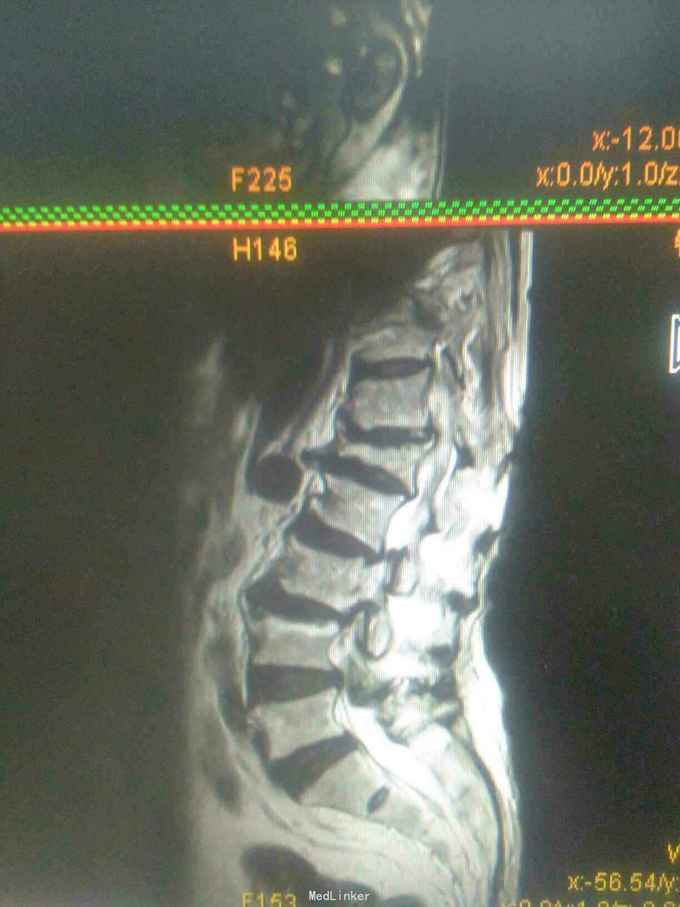

患者女,71岁,因双下肢无力,活动障碍5年余,不能行走半年。患者自诉于5年前无明显原因及诱因下逐渐出现双下肢无力,开始以双足部、双小腿为主,后整个下肢都感到无力,到入院半年前不能站立行走。大小便功能正常。

查体,双下肢肌肉萎缩,肌张力高,双侧大腿肌力3级,双小腿肌力2级,双足部肌力0级,双足部疼觉减退,会阴及双大腿、小腿感觉均正常,腱反射未引出,肛门反射、腹壁反射可引出,肛门括约肌未见松驰,双上肢查体正常。

目前诊断:双下肢瘫痪查因。

请教各位同行老师,这个考虑是什么问题,需要进一步完善什么检查。